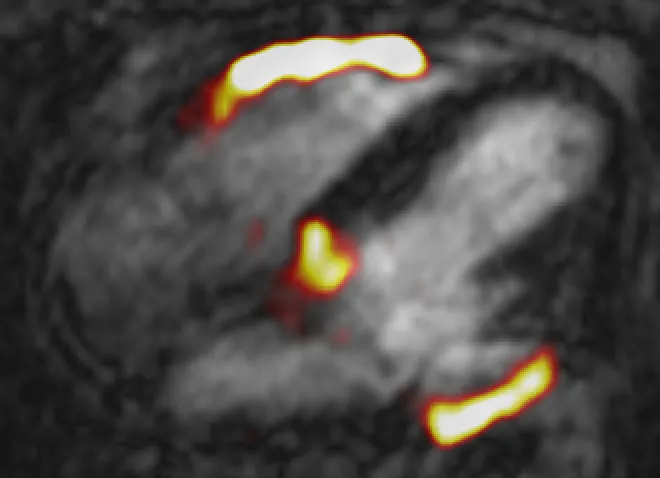

Fused 68Ga-FAPI positron emission tomography (PET) & cardiovascular magnetic resonance (CMR) of inferior wall ST-elevation myocardial infarction (MI). Apical 4 chamber view used with PET signal demonstrates intense 68Ga-FAPI uptake not only within the inferior wall (maximum tissue to background ratio [TBRmax] 3.4) but also the right ventricular free wall (TBRmax 2.4), suggesting ongoing right ventricular scarring therefore involvement in the index MI.

Reviewing the initial results, I am confident that 68Ga-FAPI PET-MR will teach us lots about the scarring process within the myocardium as well as the remainder of the cardiovascular system, something that remains incompletely understood. One example is that many cases have demonstrated right ventricular FAPI uptake. Existing evidence would suggest that the right ventricle is involved in only around 1 in 5 heart attacks affecting the inferior wall, but we have identified FAPI uptake in a far greater proportion of similar cases than this suggesting this is more common (see figure). Imaging myocardial scar outside the left ventricle has always been challenging and it is very exciting indeed to see FAPI appear to overcome the issues encountered by other currently fibrosis detection techniques including late gadolinium enhancement and T1 mapping.